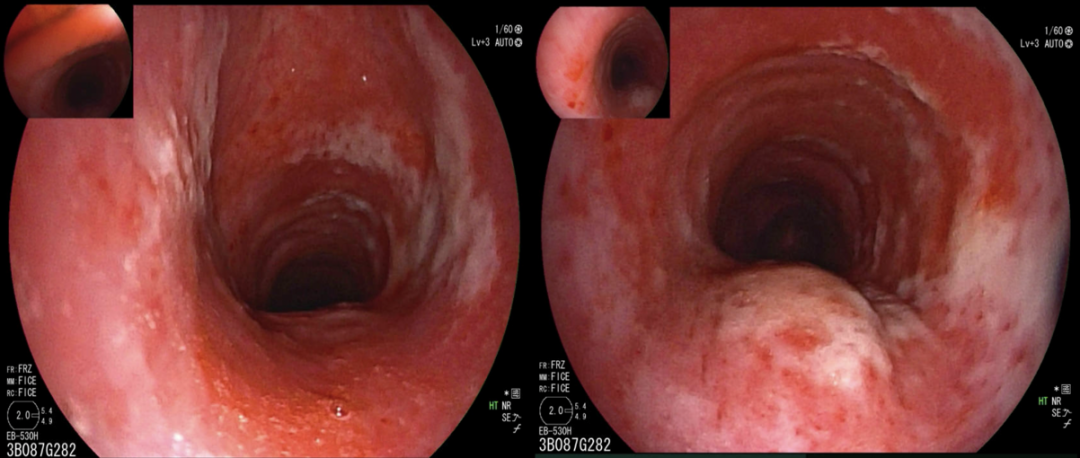

气管镜检查

患者入院后24小时内氧合急剧恶化,呼吸频率38次/分,呼吸窘迫明显。10月26日行气管插管,插管后气管镜下见两侧支气管充血,有黄白色分泌物(图4)

图4  气管镜检查